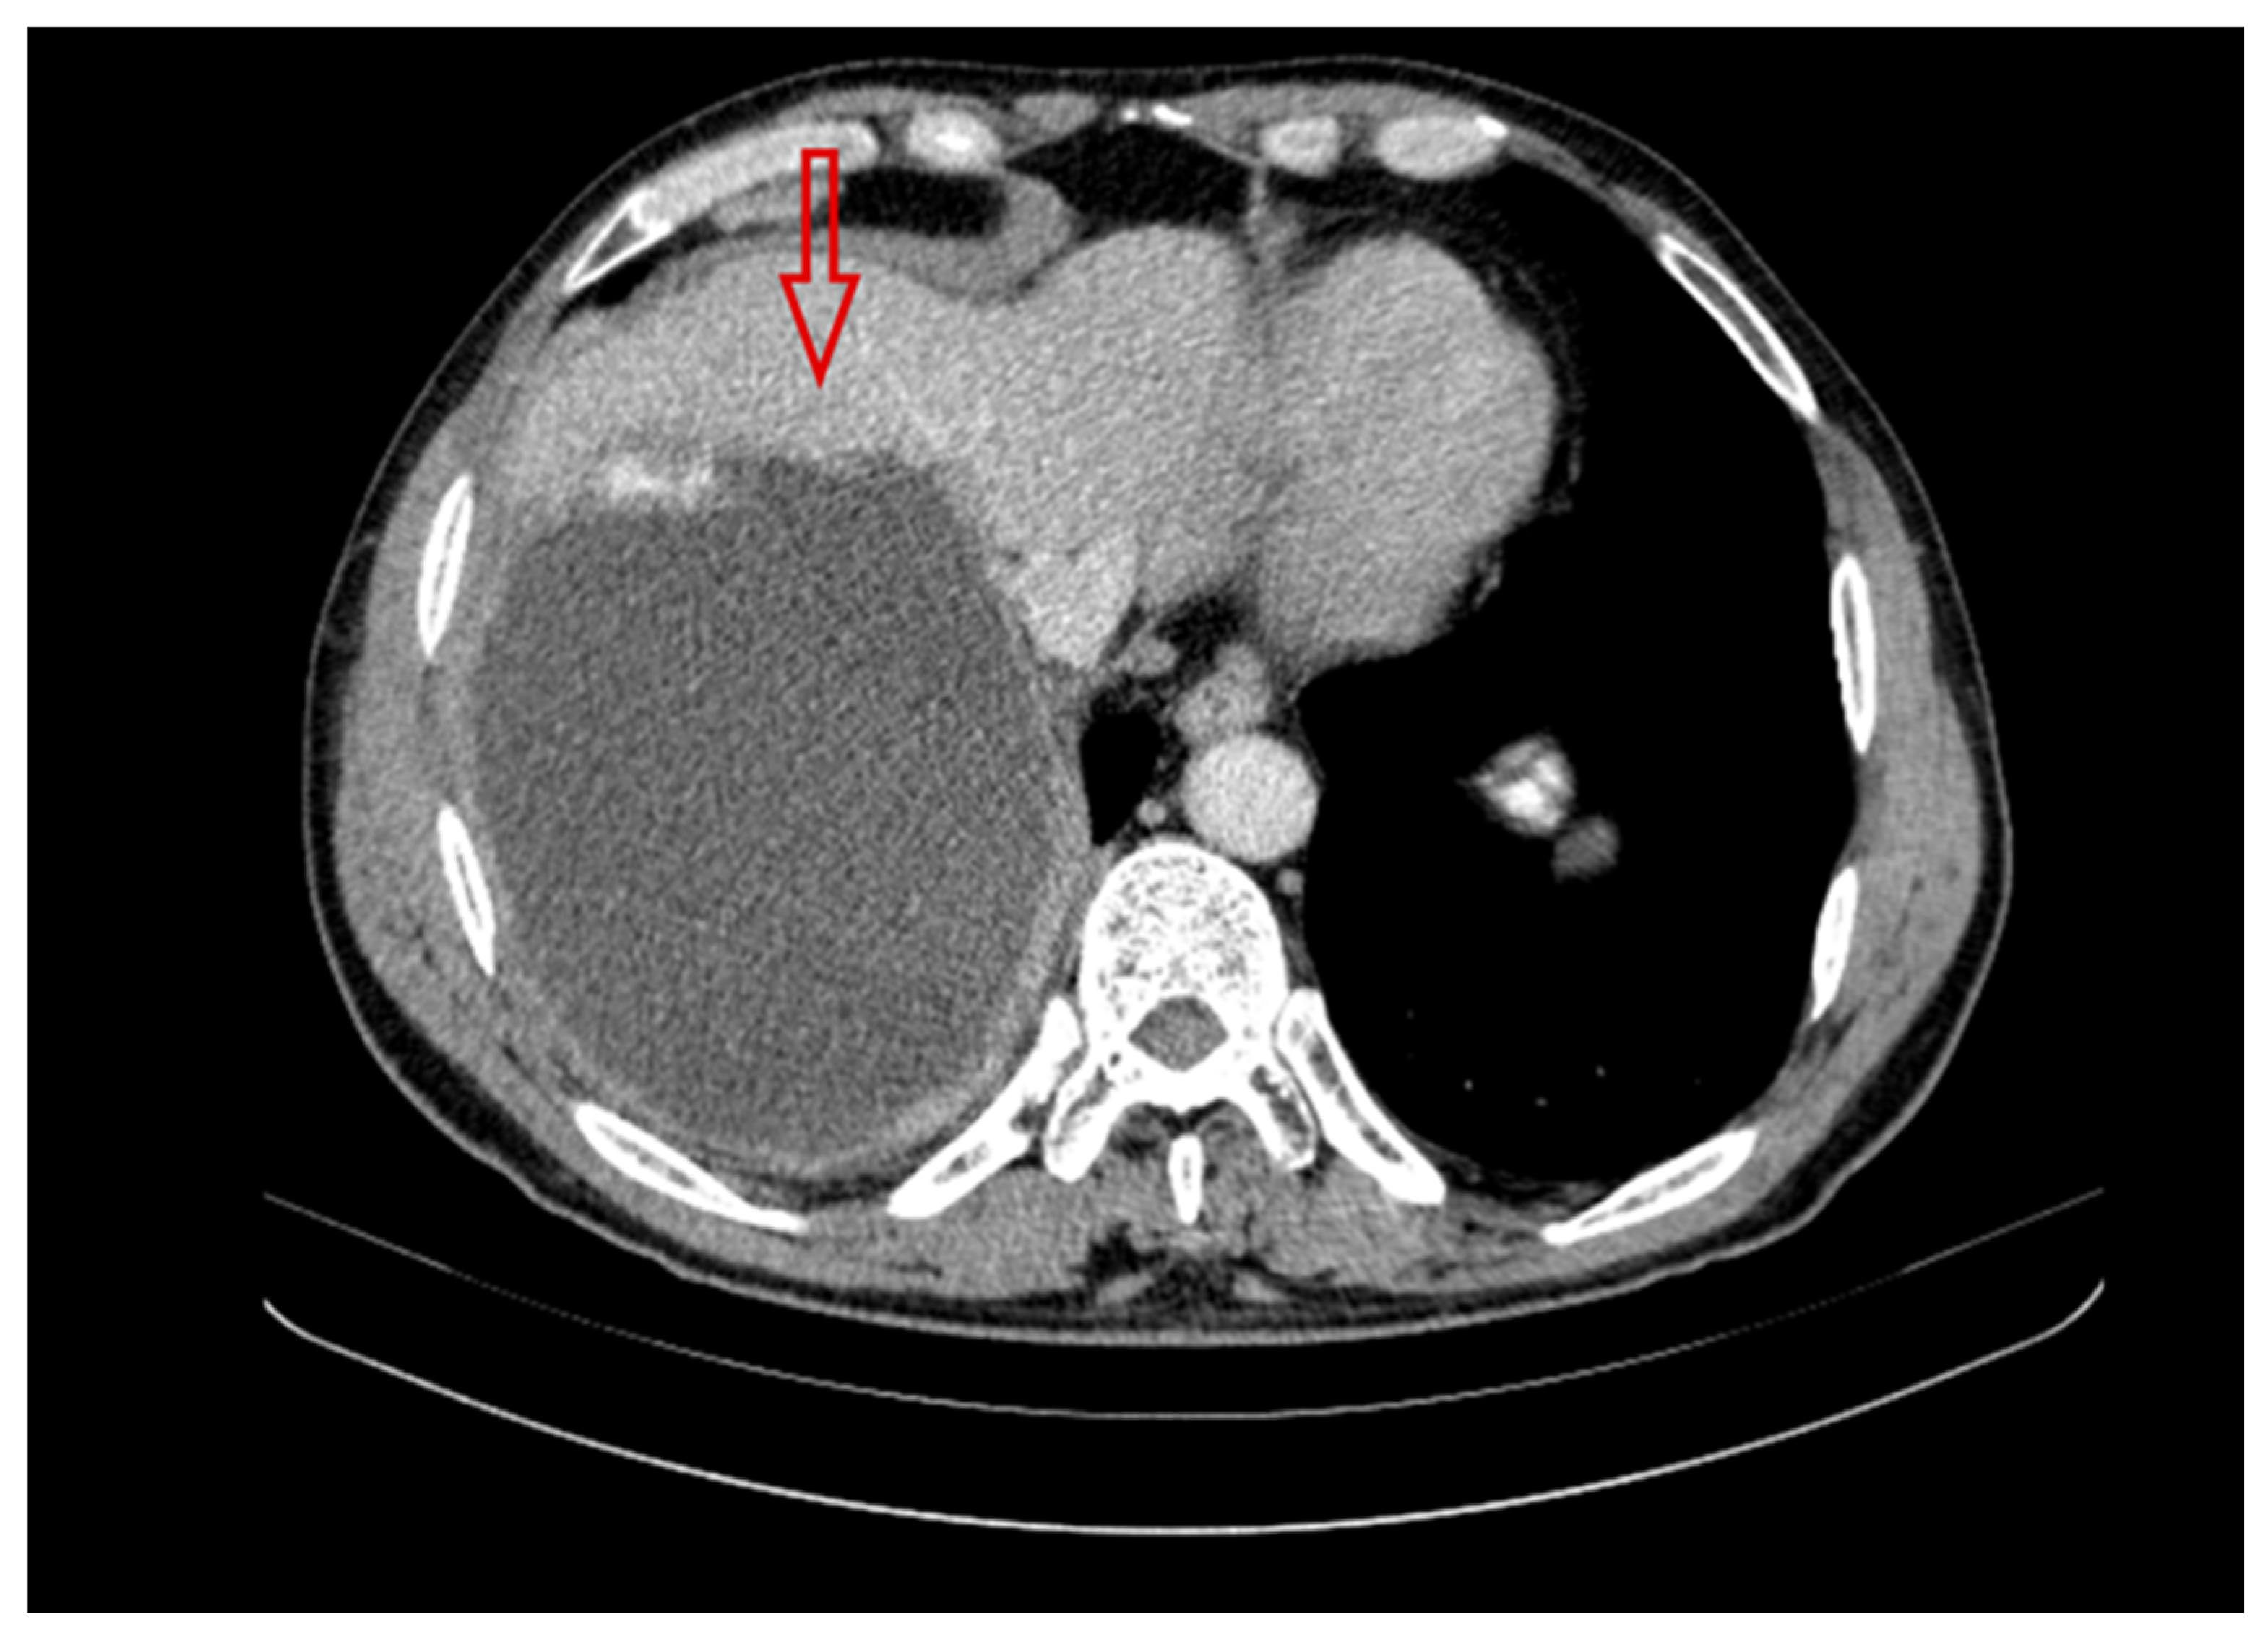

2.1. First Year of Diagnosis and Treatment of a Patient with Liver Alveolar Echinococcosis